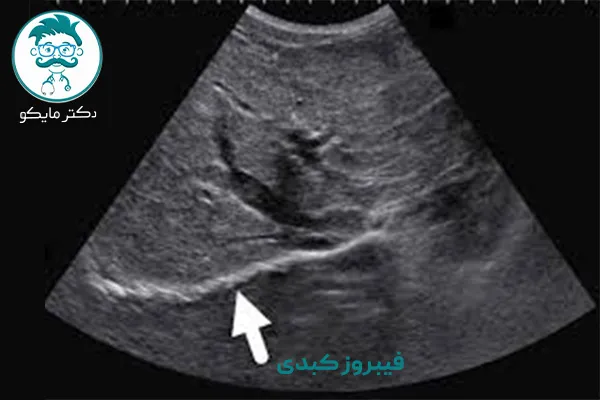

فیبروز کبدی یک فرآیند پاتولوژیک است که به تجمع تدریجی بافت اسکار در کبد منجر میشود. این اتفاق زمانی رخ میدهد که اندام سعی میکند سلولهای آسیب دیده را در حضور آسیبهای التهابی مزمن یا سایر آسیبهای مکرر به اندام، ترمیم یا جایگزین کند.

در فرآیند فیبروز، سلولهای کبدی آسیب دیده با گرههایی سخت جایگزین میشوند که در درازمدت، ساختار کبد را تغییر داده و از عملکرد صحیح آن جلوگیری میکنند. در مراحل اولیهی بیماری جلوگیری از فیبروز کبدی امکان پذیر است، اما اگر فرآیند پاتولوژیک دائمی شود خطر تکامل به سیروز کبدی که یک بیماری دژنراتیو است و میتواند منجر به مرگ شود وجود دارد. در این مطلب از دکتر مایکو به بررسی فیبروز کبد میپردازیم.

پزشکان با ترکیبی از آزمایش خون و تصویربرداری میتوانند پیشرفت فیبروز را زیر نظر داشته باشند.